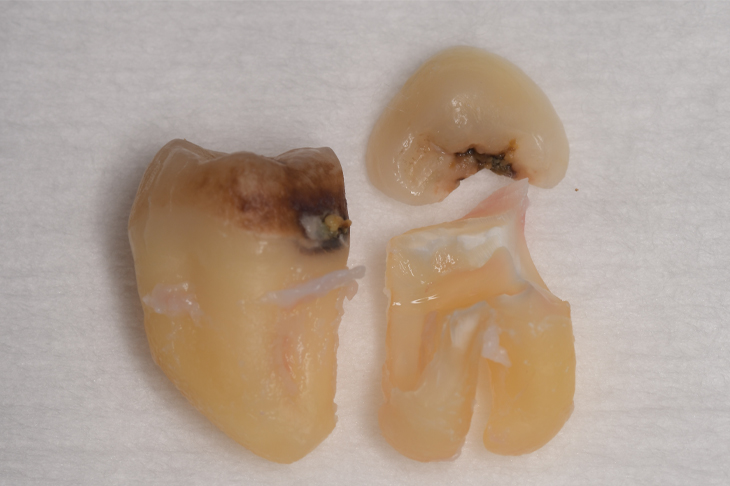

CASE 1

| 年齢・性別 | 30代・女性 |

| 主訴 | 左右に分けて親知らずを抜きたい、できれば痛くなく抜きたい |

| 親知らずのはえ方 | 完全に出ていてまっすぐはえている |

| 抜歯期間 | 15分 |

| 抜歯費用 | 約2,000円(保険内) |

| 抜歯内容 |

何度か虫歯になり痛みはないが早めに抜きたい。 完全に頭が出ているため歯ぐきを切ったり骨を削らずに抜歯しました。 根の形も単純なため抜歯自体は5分もかからず上下ともに終わりました。 術後痛みや腫れも出ていません。 抜歯後は感染をしやすいため必ず抗生物質を飲み切ってください。 |